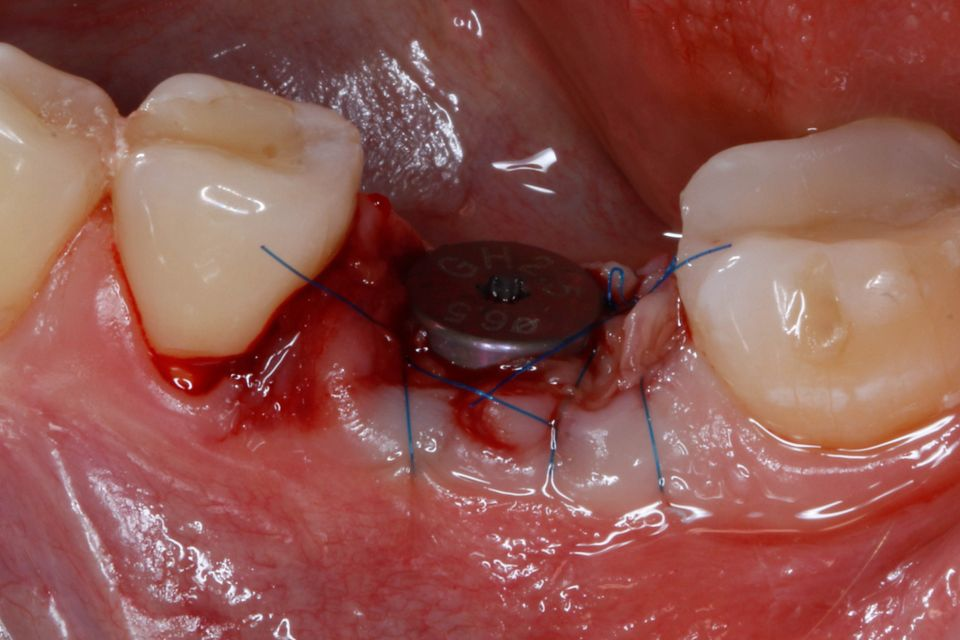

#36 牙的手术过程从局部麻醉和下牙槽神经阻滞开始。通过分割磨牙根实现无翻瓣反射的无创拔牙;从而保留肺泡壁和根间隔膜(图3-4)。仔细清洁牙槽,形成种植体路径并放置Straumann ® BLX 种植体 5.5 x 8 mm (图 5-7)。为了促进非浸没式愈合,将标准愈合基台连接至种植体。骨壁和种植体之间的间隙填充有同种异体骨材料颗粒(maxgraft®,botiss 生物材料,德国)。应用富含血小板的纤维蛋白(PRF)来实现适当的初步愈合。调整软组织边缘并用聚丙烯 6/0 缝合,使愈合基台暴露(图 8-9)。将粘性牙周Reso-Pac ®敷料(来自德国杜伊斯堡的Hager & Werken)放置在治疗区域上以协助愈合过程(图10)。

图6